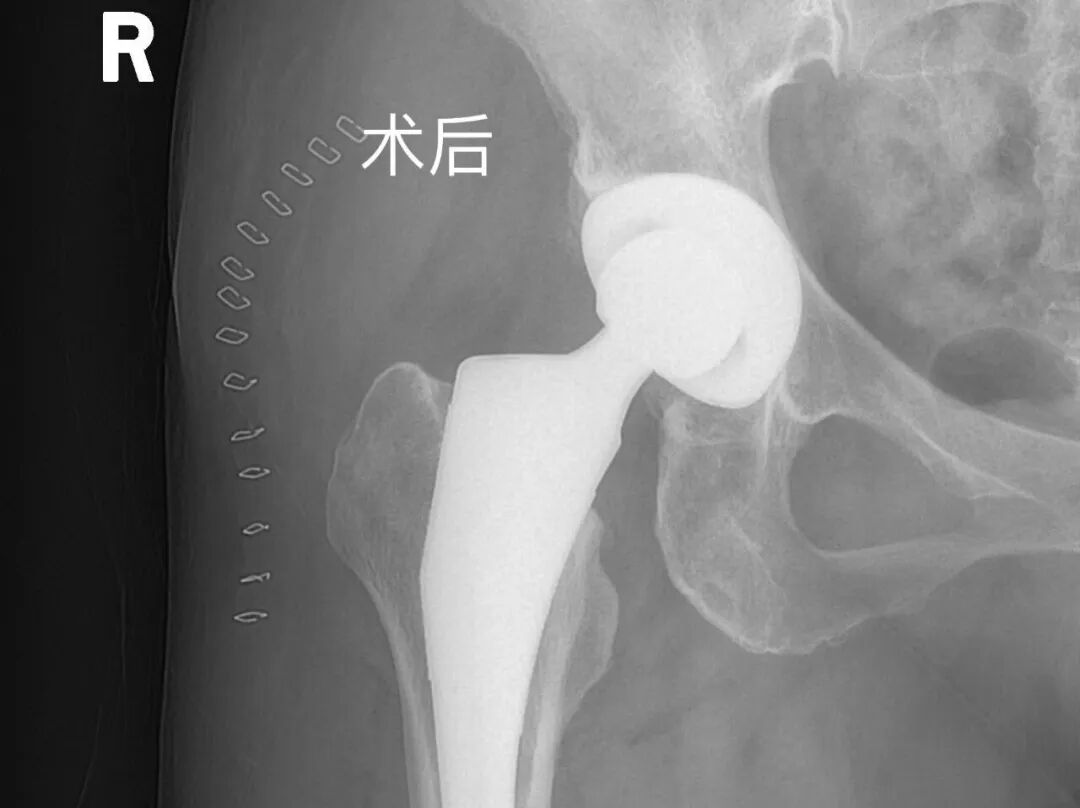

幸运的是,七病区为她带来了希望。科室主任王剑锋带领团队,为她开展了右全髋关节置换术。术后,冯女士在医护人员的指导下,慢慢找回了走路的感觉。一个月后复查,冯女士笑着说:“现在走路、上下楼都不在话下,感觉像重新活了一遍!”